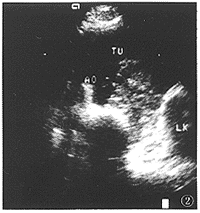

图2 上腹横切面。肿块(TU)位于腹主动脉(AO)和左肾(LK)之间。内部回声不均,边界不清楚和不规则,无移动性,AO被包绕。超声引导下活检诊断为神经内分泌癌。